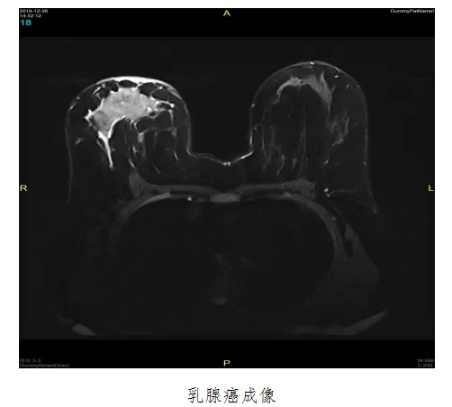

乳腺癌是我国近几年来发病率增速最快的癌症之一,严重危害女性的身心健康。如果能够早期发现并及时治疗,患者5年生存率可达70%。而磁共振乳腺成像的优势恰恰在于早发现,其对于乳腺癌早期诊断具有重要临床价值。我院超导1.5T磁共振已引进乳腺线圈,乳腺磁共振扫描现已为常规检查及体检项目,填补了安达医疗的空白。

1. 乳腺增生性病变、囊肿、腺瘤、乳腺癌等;

2. 评价钼靶或超声检查发现的可疑病变;

3. 乳腺癌的分期及评估新辅助化疗疗效;

4. 判断乳腺癌术后有无复发;

5. 高发人群乳腺癌的筛查,如乳腺癌家族史;

6. 乳腺内增生结节过多或腺体致密的女性;

7. 乳房成形术后对植入假体的评估及随访;

8. 乳头溢液、溢血的患者;